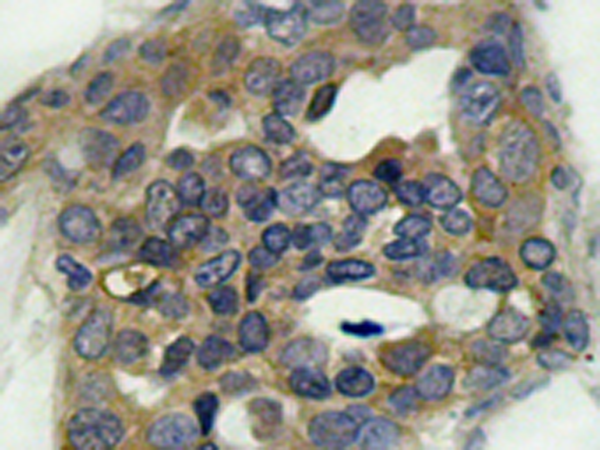

IHC positive control:

Human breast carcinoma

IHC Recommend dilution:

50-100